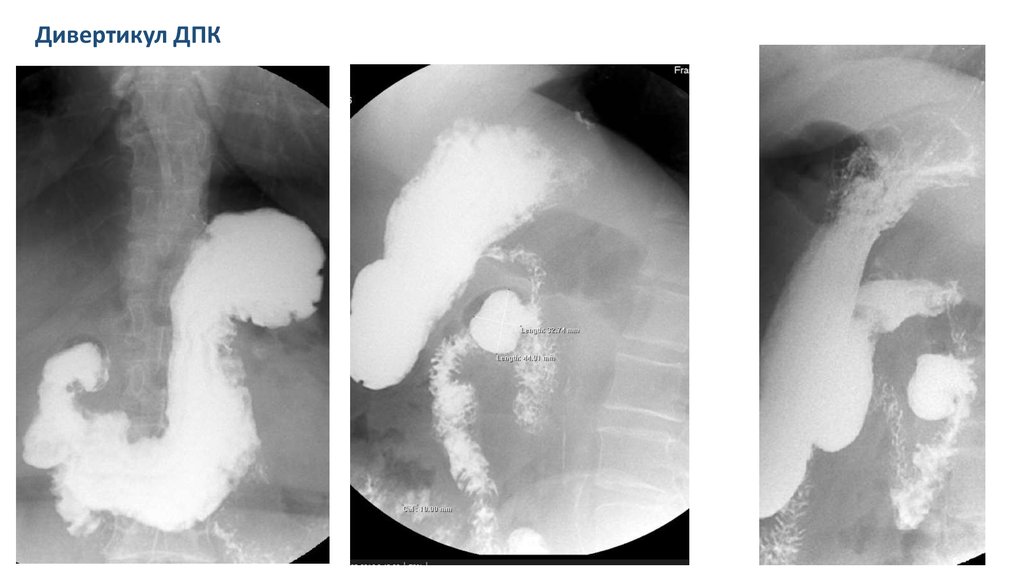

Дивертикул ДПК